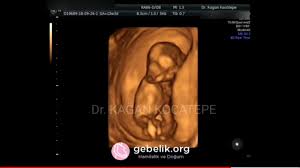

13 5 haftalik 3 aylik bebek ultrason goruntuleri aciklamali boyu nedir cinsiyet belli olur mu youtube